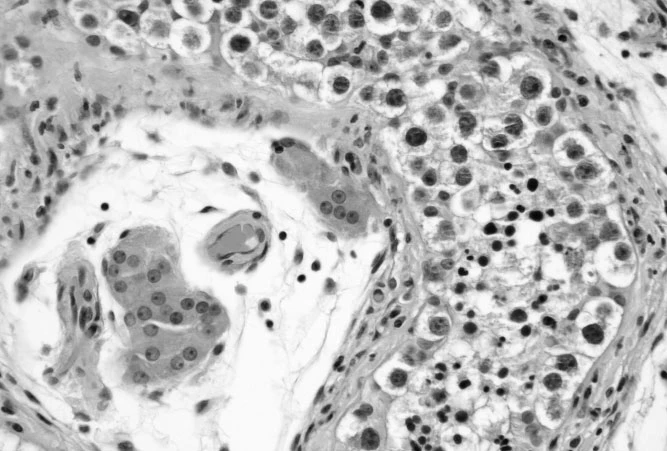

Carcinoma

Carcinoma is the most common type of cancer, and it originates from epithelial cells (cells that cover the inside and outside surfaces of the body).